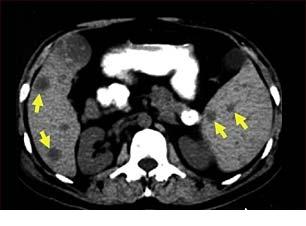

Cancerul colorectal - generalitati